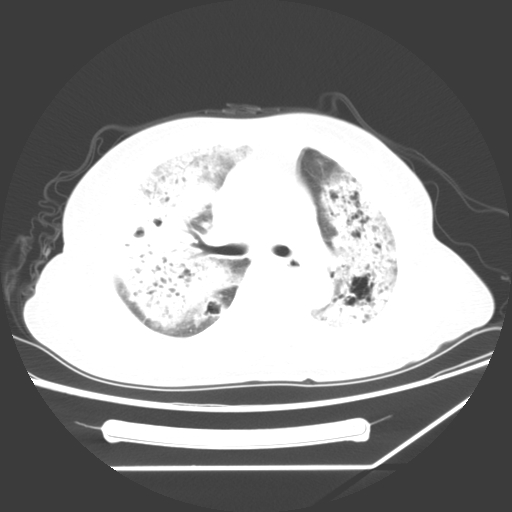

标题: CT25393:病人45岁,咳嗽,吐黄痰带血丝,发热,胸闷月余 [打印本页]

标题: CT25393:病人45岁,咳嗽,吐黄痰带血丝,发热,胸闷月余

1、左肺中央型肺癌并双肺弥漫性转移   2、双肺部感染    3、肺大泡     4、左侧胸腔积液

双侧肺弥漫性病变,可见“空泡征”及“蜂窝征”,考虑肺泡癌可能性大,左侧胸腔积液,考虑胸膜受累可能!

考虑肺泡癌,建议排除感染。

考虑肺泡癌

1)不排除肺泡癌可能。2)左侧胸腔积液。